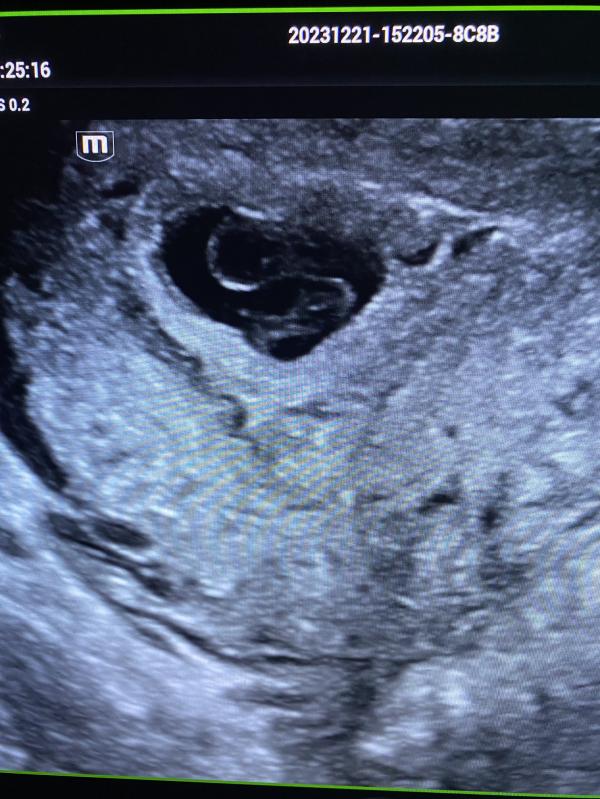

На 3 фото нежеланная беременность 8 недель.